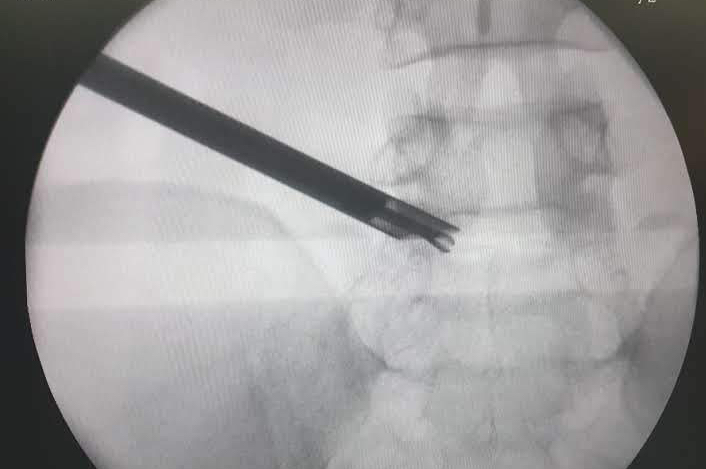

Is it safe? : Lumbar endoscopic or micro-discectomy surgery is an very safe procedure that is routinely performed by spine surgeons. The use of microscope or endoscope help to visualise the structures with greta magnification during surgery and that significantly reduces the risk of nerve root injury or spinal fluid leakage.

Transforaminal endoscopic discectomy can also be done under local anaesthesia, making it suitable for the patients who may be at high risk for general anaesthesia due to other medical conditions causing compromised heart or lung function.